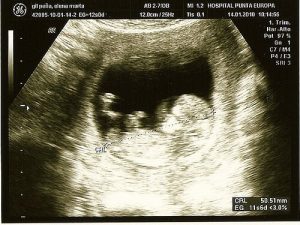

Echografie:

Dit is een zeer algemene procedure. Het is zowel nuttig om problemen op te sporen als om je baby voor het eerst te zien.

Met deze procedure kan het geslacht van de baby worden vastgesteld. Het maakt ook de vroege opsporing van afwijkingen, zoals hartafwijkingen en chromosomale veranderingen, mogelijk.

Een echografie is een onderzoek dat wordt aanbevolen om mogelijke afwijkingen van de foetus nauwlettend in de gaten te houden. Een echografie wordt aanbevolen wanneer andere routine-onderzoeken op mogelijke afwijkingen.

Het is een niet-invasieve techniek waarbij beelden worden verkregen door een apparaat met behulp van geluidsgolven. Deze golven doen je baby geen pijn. Ze maken het mogelijk de binnenkant van je baarmoeder te zien.